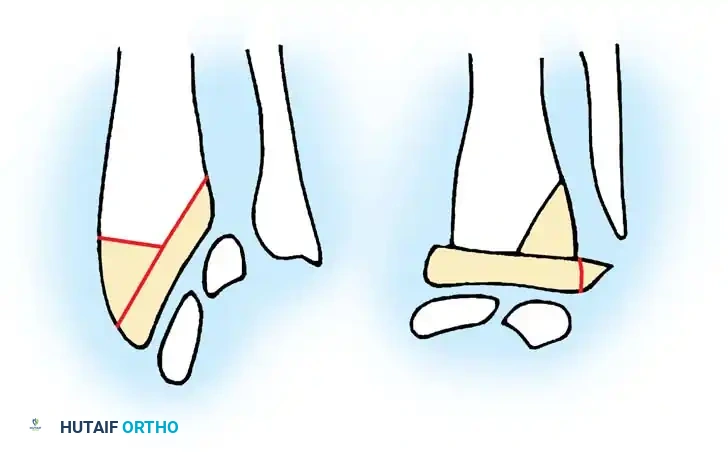

Diagrammatic representation of the A1 pulley release, ensuring the A2 pulley remains intact to prevent bowstringing.

Biomechanical illustration showing the relationship of the FDS and FDP tendons within the digital sheath.